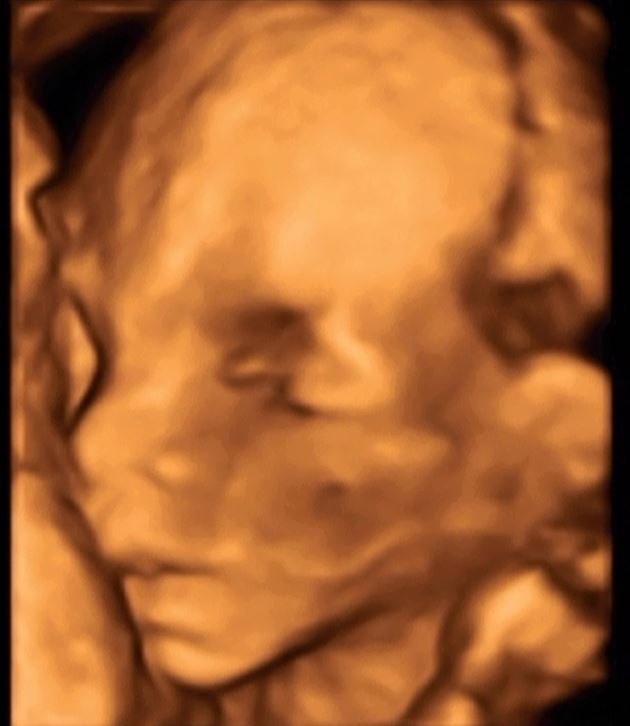

Przedstawiam Jana :D na ostatnim zdjęciu wiecie co... :D